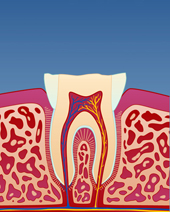

figur II

Slitasjen er spesielt tydelig i overkjeven.